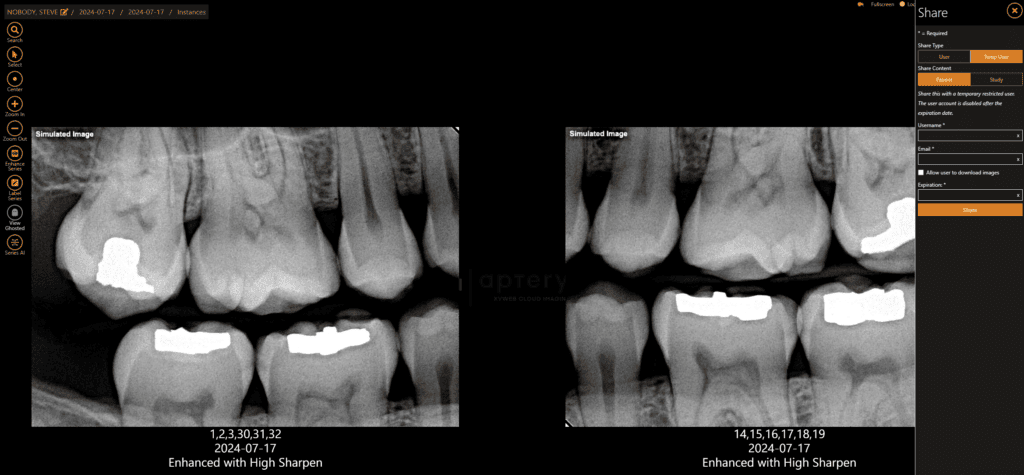

Secure Imaging Transfer and Collaboration

Effortlessly share images with colleagues and specialists using Apteryx’s secure imaging-sharing portal. Enhance patient care, streamline referrals, and protect patient data and your practice’s reputation with our secure cloud-based solution. Collaboration is a breeze with Apteryx.

DICOM Image Formatting

The ability to upload, store and share your patient’s image data with other dental or medical professionals can make or break a treatment timeline. Digital Imaging and Communications in Medicine (DICOM) practices were created to address this necessity.